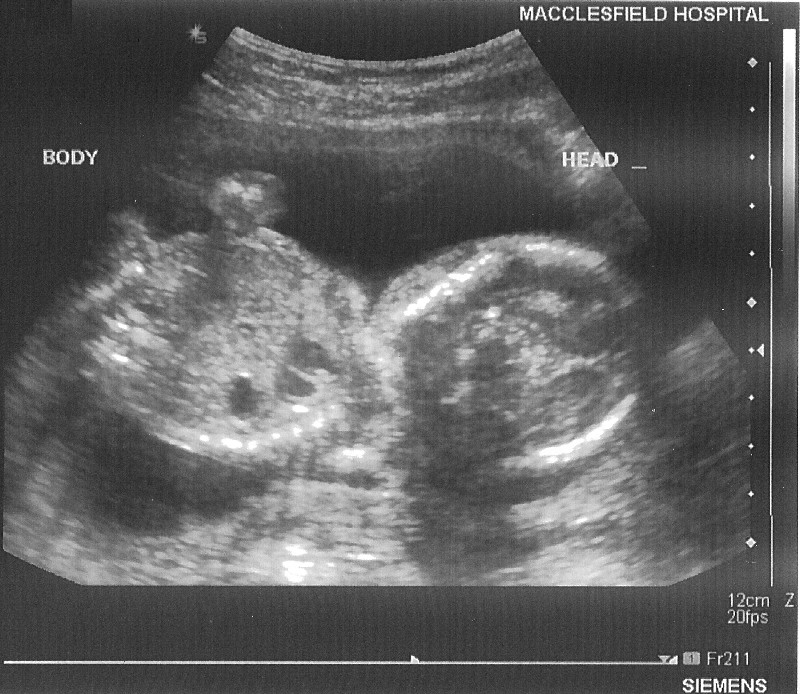

20 Week Hospital Scan on 14 March 2006